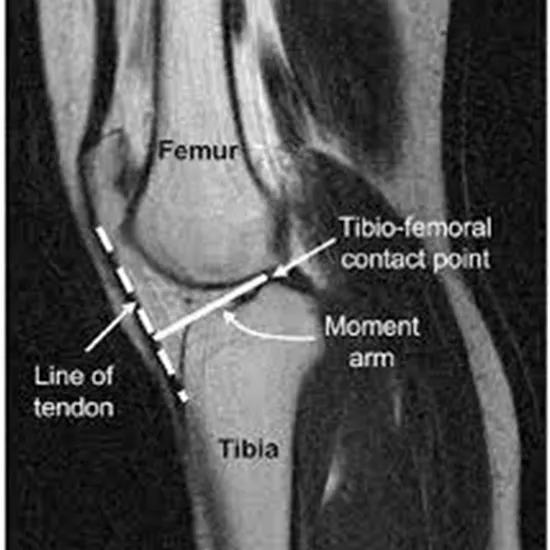

An MRI screening of the left knee joint is a diagnostic imaging procedure that uses a powerful magnetic field and radio waves to produce detailed images of the internal structures of the left knee joint. This test helps doctors diagnose a wide range of knee problems.